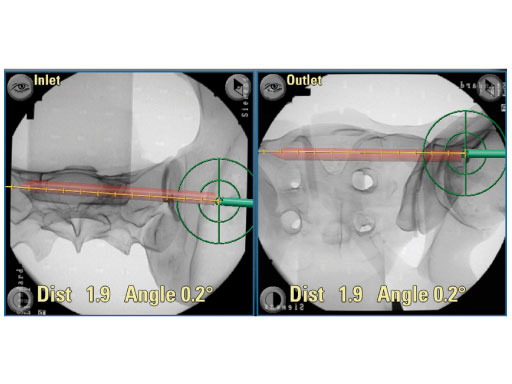

The Posterior Pelvic Ring Fixation Module guides surgeons through the complex anatomy of the pelvis during a screw fixation of the posterior pelvic ring. An easy-to-use interface enables intuitive planning and insertion of sacroilliac screws, based on multiple intraoperatively obtained C-arm images. The display simultaneously shows the surgical instruments in all relevant views (inlet, outlet, AP and lateral), and the surgeon is safely guided to the desired target position. This virtual fluoroscopy also substantially reduces radiation time, and is particularly useful for C-type fractures, according to the Mller AO Classification.